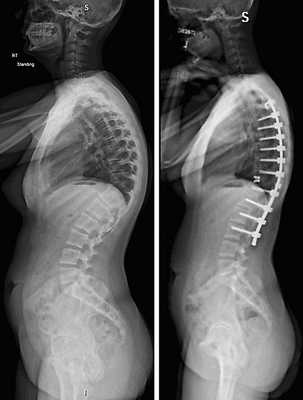

Пациенту по поводу спондилолизного спондилолистеза выполнена декомпрессия и позвоночно-тазовая стабилизация системой expedium

Рентген до операции

Фото транспедикулярной фиксации позвоночника

Рентгеновского снимка после операции

Коррекция кифоза грудного отдела.